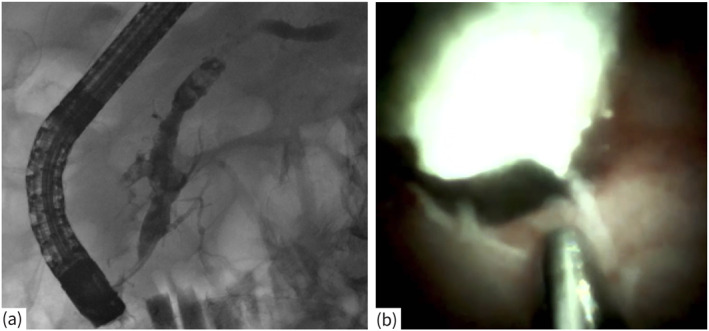

Introduction: Ductal decompression has become the main approach for treating patients with symptomatic chronic calcifying pancreatitis and signs of ductal hypertension. Digital single operator video pancreatoscopy (dSOVP) has shown high success rates when compared with more established techniques such as extracorporeal shock wave lithotripsy. However, there is still limited evidence on long-term clinical success and quality of life.

Methods: Patients with chronic calcifying pancreatitis who underwent digital single operator video pancreatoscopy guided electrohydraulic lithotripsy (EHL) of pancreatic duct stones with initial technical and clinical success were recruited for this retrospective, multicenter cohort study. Persistence of clinical success (defined as pain reduction > 50% in numerical rating scale [NRS]) as well as postinterventional quality of life (QOL) were retrospectively evaluated by database analysis and with QOL using the Mental and Physical Condition Scores (MCS, PCS).

Results: A total of 58 patients were included in the long-term follow-up conducted over 24 months. Significant and sustained pain relief was reported in 70.7% of patients (n = 41) at month 3; this effect persisted until month 24. MCS decreased from 50.36 ± 13.3 at baseline to 49.75 ± 11.1 at month 12 with no statistically significant difference (data available for 42 patients, p = 0.15). Similarly, the PCS showed no significant improvement, remaining constant at 44.9 ± 9.8 at baseline and 44.9 ± 10.8 at month 12 (p = 0.1). The overall adverse event rate was 26% (11 patients), primarily consisting of mild to moderate pancreatitis (n = 9, 22%).

Conclusions: Digital single operator video pancreatoscopy guided lithotripsy was shown to be safe and effective in a long-term follow-up regarding pain control but had no significant influence on QOL. Complete stone removal seems to be the key point for long-term clinical success.